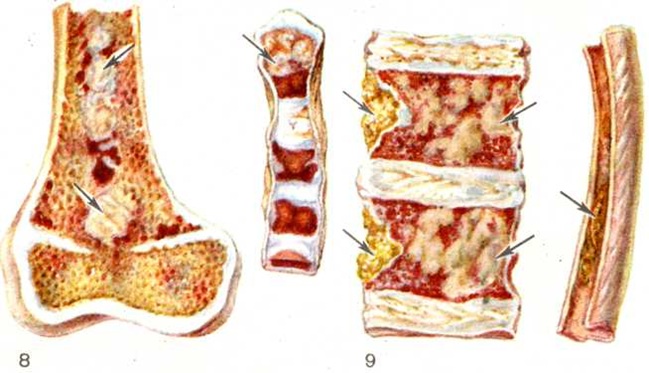

При вскрытии наиболее типичные изменения обнаруживаются в плоских и иногда трубчатых костях. Они хрупкие, мягкие, нередко режутся ножом. Могут наблюдаться переломы, деформация костей, в частности компрессия тел позвонков, иногда со сдавлением спинного мозга. При диффузно-узловатой форме Миеломная болезнь, которая при развёрнутой картине болезни встречается наиболее часто, костный мозг на разрезе имеет пёстрый вид, содержит множественные серовато-розовые узловатые разрастания различной величины (цветной рисунок 8). В узлах и вокруг них вследствие кровоизлияний и некрозов нередко выявляются темно-красные и желтоватые участки. Опухолевые массы иногда прорастают в прилежащие ткани (мышцы, кожу, плевру, твёрдую мозговую оболочку и так далее). При диффузной форме Миеломная болезнь костный мозг сочный, пёстрый из-за чередования разрастаний плазматических клеток, кровоизлияний, некрозов. Число костных пластинок уменьшено, кортикальный слой истончён. В редких случаях остеопороз отсутствует. Размеры и вес селезёнки, печени, лимфатических, узлов обычно в пределах нормы или несколько увеличены. В ряде случаев отмечается значительное увеличение их объёма вследствие массивного специфического поражения. Описаны редкие случаи развития обширных узловатых разрастаний в коже, плевре, лёгких, почках, в головном мозге и другие Почки могут быть увеличены, бледные, гладкие; при выраженных склеротических изменениях выявляется картина вторично-сморщенной почки. В ряде случаев имеются точечные и пятнистые кровоизлияния в кожу, серозные и слизистые оболочки, ткань внутренних органов. Как правило, обнаруживаются признаки общего малокровия, дистрофии паренхиматозных органов, часто гнойно-воспалительные процессы.

Электронная микроскопия плазматических клеток при Миеломная болезнь позволяет выявить гипертрофию протеин-синтезирующих структур — шероховатую эндоплазматическую сеть в виде мешков и цистерн, оттесняющих ядро к периферии, полирибосомы и развитой комплекс Гольджи. Ацидофильные тельца выявляются в виде оптически плотных гранул, содержащих аморфную белковую субстанцию. Полагают, что они состоят из конденсированного парапротеина. В связи с высоким содержанием белка и рибонуклеопротеидов цитоплазма этих клеток резко пиронинофильна, имеет ШИК-положительную реакцию, люминесцирует при окраске тиофлавином Т. Наряду со зрелыми плазмоцитами выявляются плазмобласты, атипичные гигантские одно и многоядерные клетки. Клеточный состав разрастаний варьирует в различных случаях и нередко отличается в разных участках скелета. Разрастания плазматических клеток могут быть узловатыми, диффузными или диффузноузловатыми. Первый вариант, как показывают результаты трепанобиопсии, встречается главным образом в ранние стадии болезни. При этом на фоне нормального костного мозга выявляются множественные, довольно больших размеров (от 200 микрометров и более) очаговые разрастания плазматических клеток (рисунок 2), проникающие в прилежащую ткань. Прогрессирование Миеломная болезнь характеризуется развитием диффузной инфильтрации костного мозга плазматическими клетками (рисунок 3). Нередко это сопровождается развитием обширных узловатых разрастаний (цветной таблица, ст. 33, рисунок 8 и 9). Число клеток нормального гемопоэза заметно снижено. Могут выявляться поля миелофиброза, жировых клеток. Характерно значительное истончение костных пластинок вплоть до полного их исчезновения на больших участках, расширение каналов остеонов (гаверсовых каналов), частичное разрушение коркового вещества с прорастанием плазматических клеток в надкостницу. Рассасывание костной ткани протекает по типу гладкой, пазушной и остеокластической резорбции. Полагают, что остеопороз обусловлен нарушением процессов костеобразования вследствие повышенной секреции в костном мозге фактора, стимулирующего остеокласты. Репаративные процессы резко снижены, однако в ряде случаев наблюдается очаговое образование кости примитивного строения, преимущественно в области микро-переломов и в зонах кровоизлияний по периферии узловатых разрастаний (рисунок 4). Изредка рассасывание костной ткани отсутствует, имеет место утолщение костных пластинок.